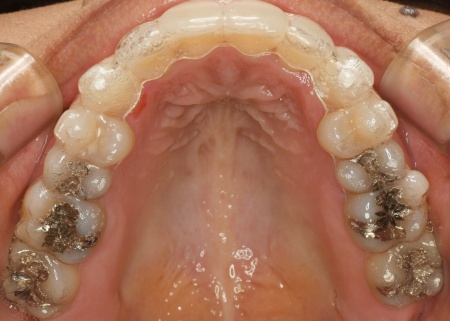

そのため、今回はマウスピース型矯正装置「インビザライン・コンプリヘンシブ」による矯正治療と、舌の癖を改善するトレーニング「MFT(口腔筋機能療法)」を併用することを提案し、同意いただきました。

インビザライン・コンプリヘンシブは、幅広い症例に対応可能で、マウスピースを段階的に交換しながら歯を少しずつ動かしていく方法です。

今回は、奥歯を少し押し込みながら前歯が噛み合うように治療を行う方針です。

最後に、歯並びが整い前歯で噛めるようになったこと、舌の癖が改善されたことを確認し、治療を終了しています。